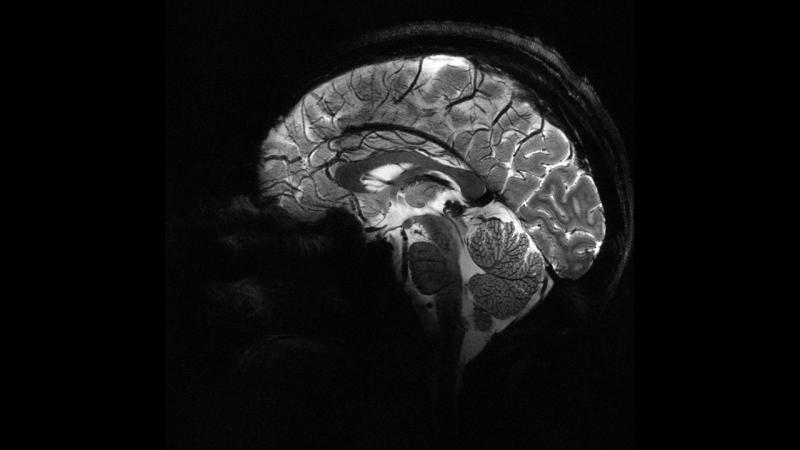

Beyinə tətbiq olunan elektrik cərəyanları eqoizmi azalda bilərmi?

7News.az xəbər verir ki, Sürix Universitetində aparılan yeni araşdırma, beynin iki fərqli sahəsini stimullaşdırmaqla insanları daha az eqoist etmənin yolunu tapıb.